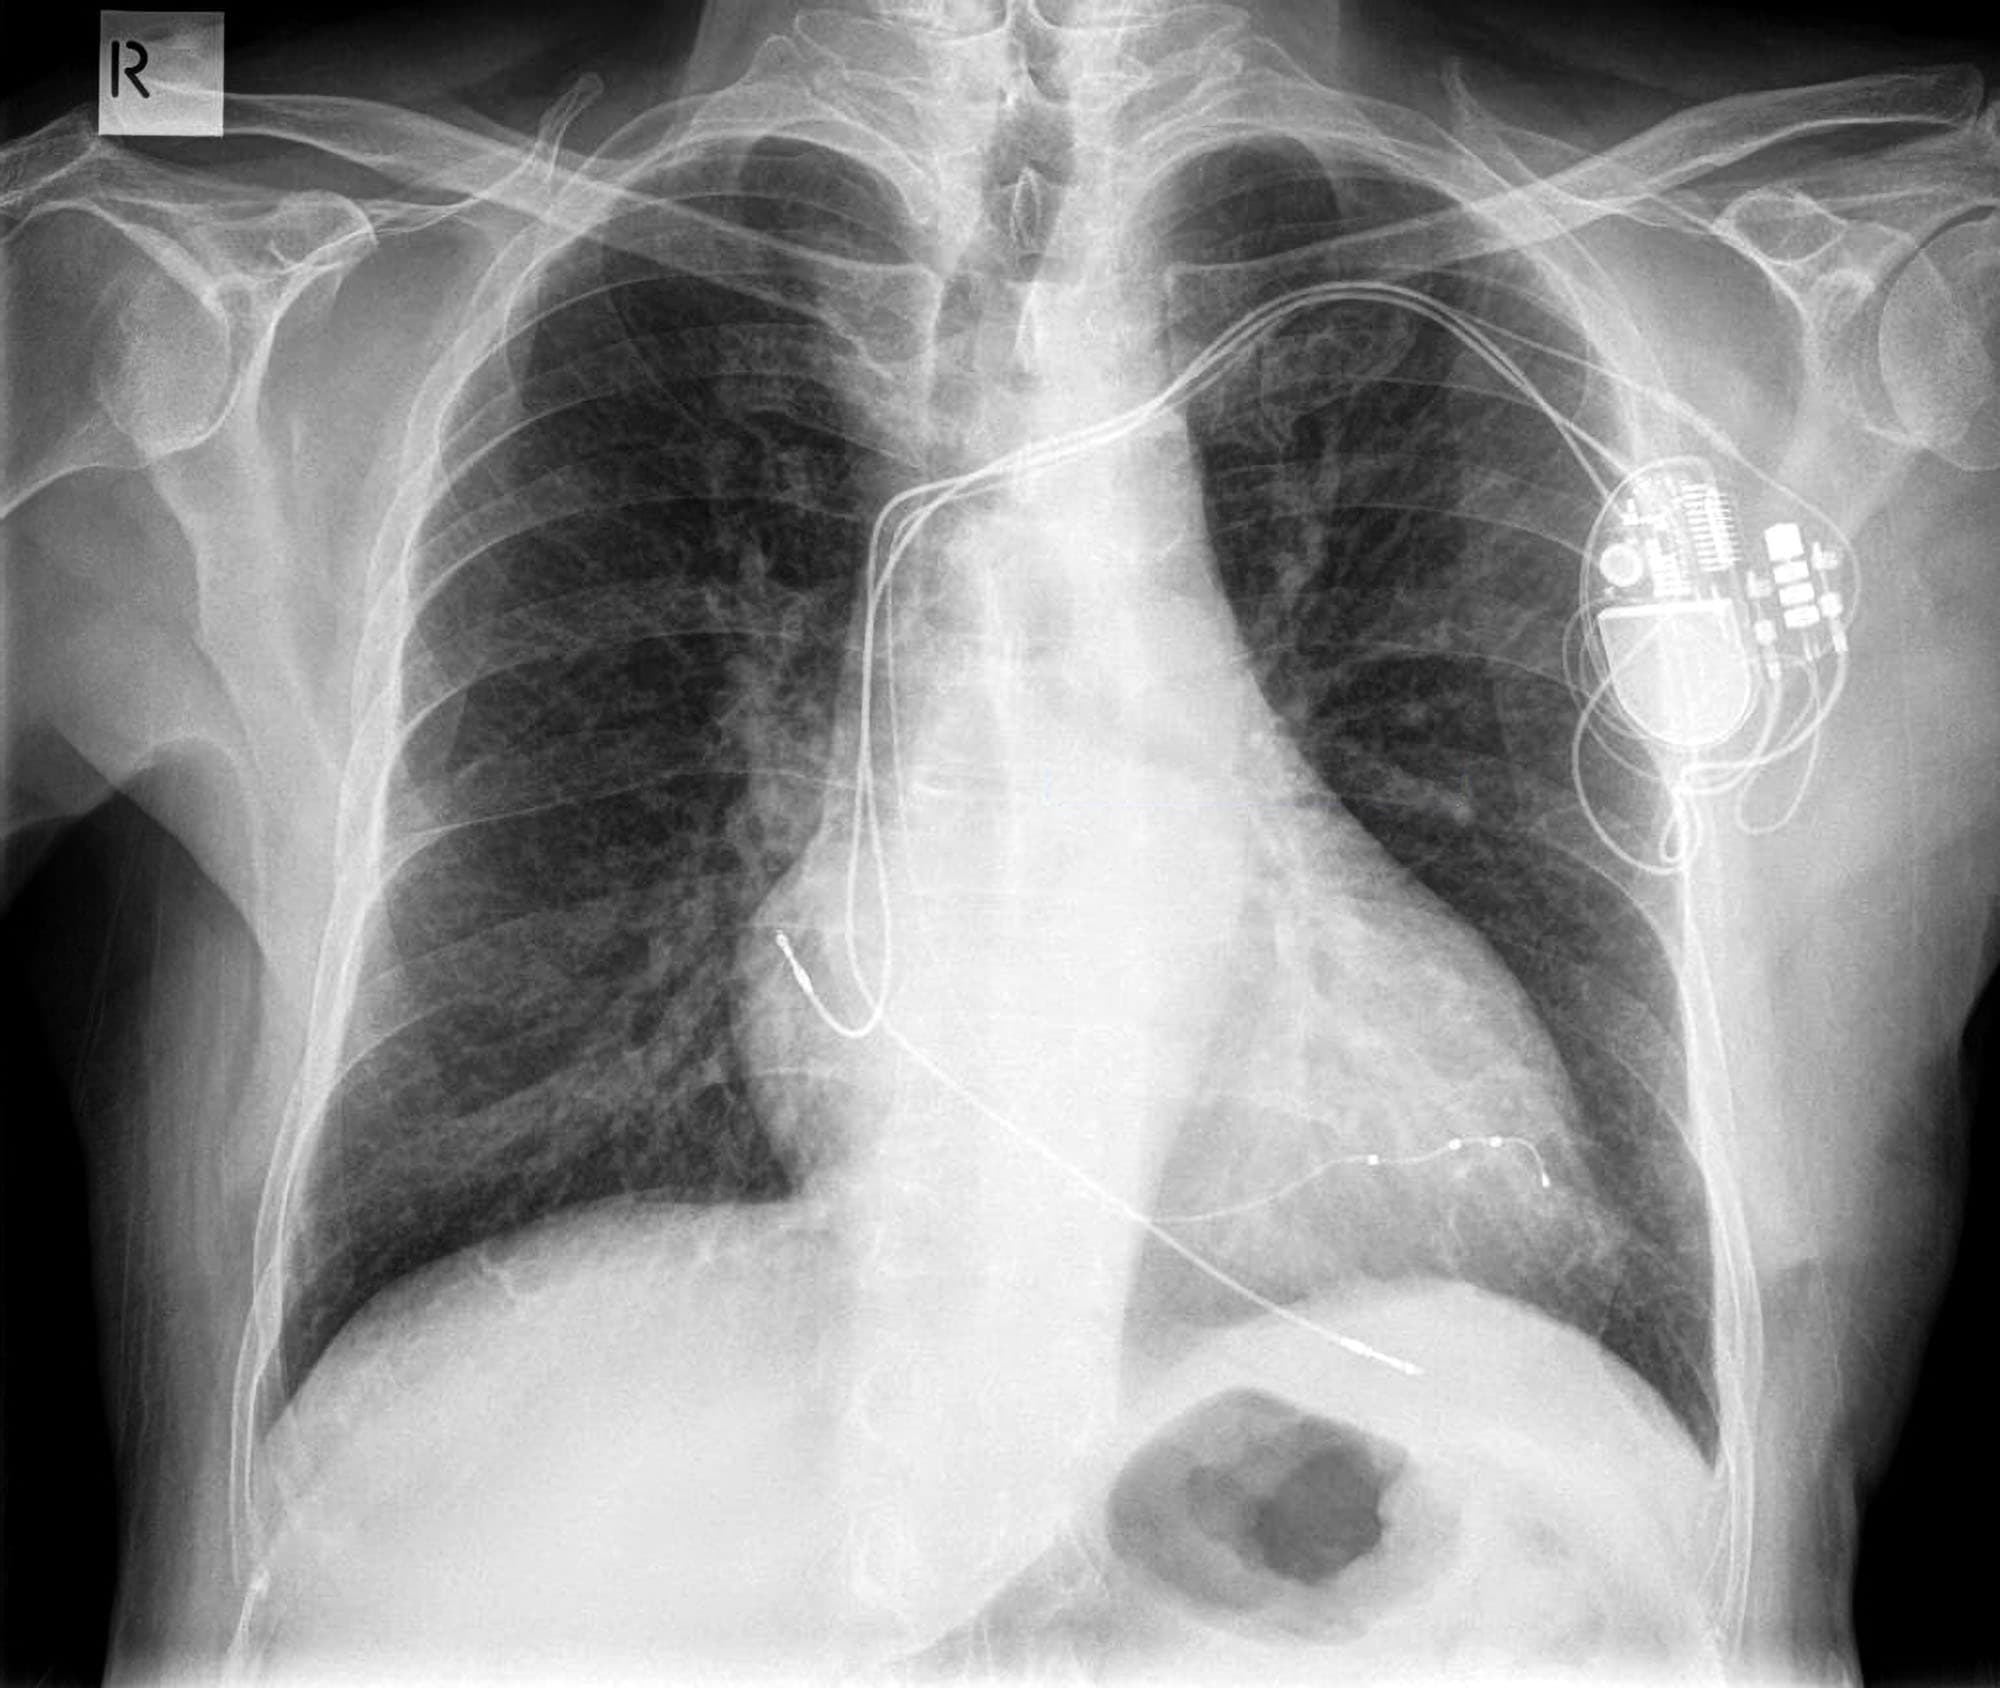

CRT

crt.jpg